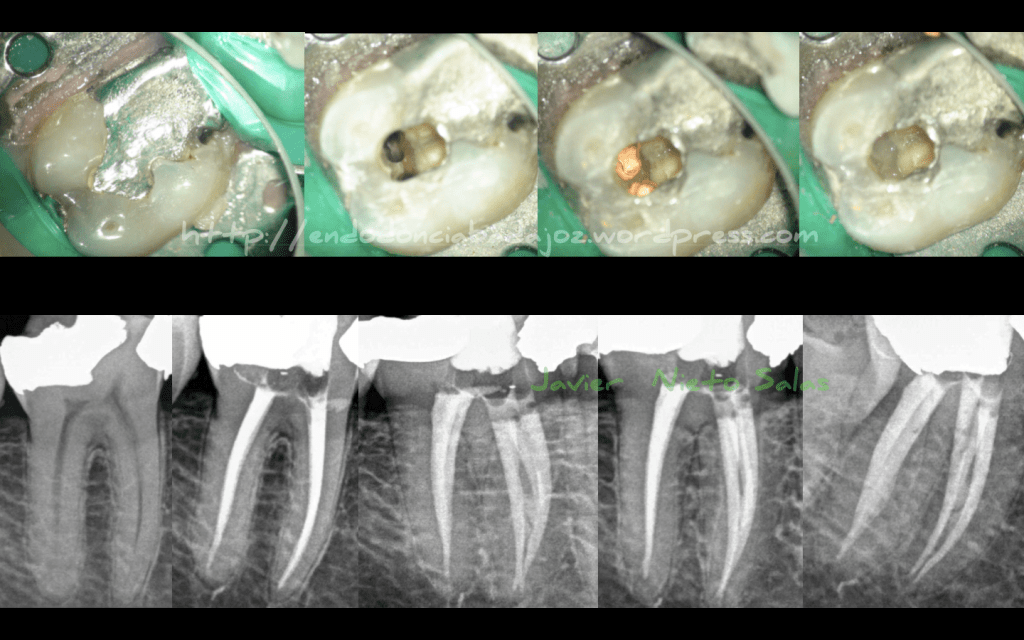

Hoy en día se está hablando demasiado de las «Aperturas Ninja», creo que es un concepto equivocado, se trata de llamarlo «apertura conservadora» que consiste en estudiar el caso y ver la cantidad SUFICIENTE y MÍNIMA para realizar un correcto tratamiento de conductos. Entre las ventajas, se encuentra conservar mayor estructura dentinaria que es tan importante para supervivencia del diente en el tiempo. Y como desventaja principal, que se complica el tratamiento mucho, en cuanto a desinfección , conformación y obturación de conductos.

Sigo apostando por esta «apertura conservadora»:

La anatomía de los molares inferiores es bastante aberrante, sus anastomosis entre conductos, bifurcaciones y demás hacen de esta pieza una de las más complicadas de tratar. Estas que colocamos no son casos complicados, pero de igual forma hemos intentado manejarlos correctamente.

Este caso tiene la particularidad de tener 5 conductos, 3 mesiales y dos distales. Se trata de un 4.7 con una necrosis pulpar con periodontitis apical asintomática. Se instrumentó con Reciproc y Mtwo. El conducto Distal se talló también con ultrasonidos. La técnica de obturación fue con Condensación Vertical con Ola continua de calor modificada y un backfilling con sistema de gutapercha inyectada de B&L.